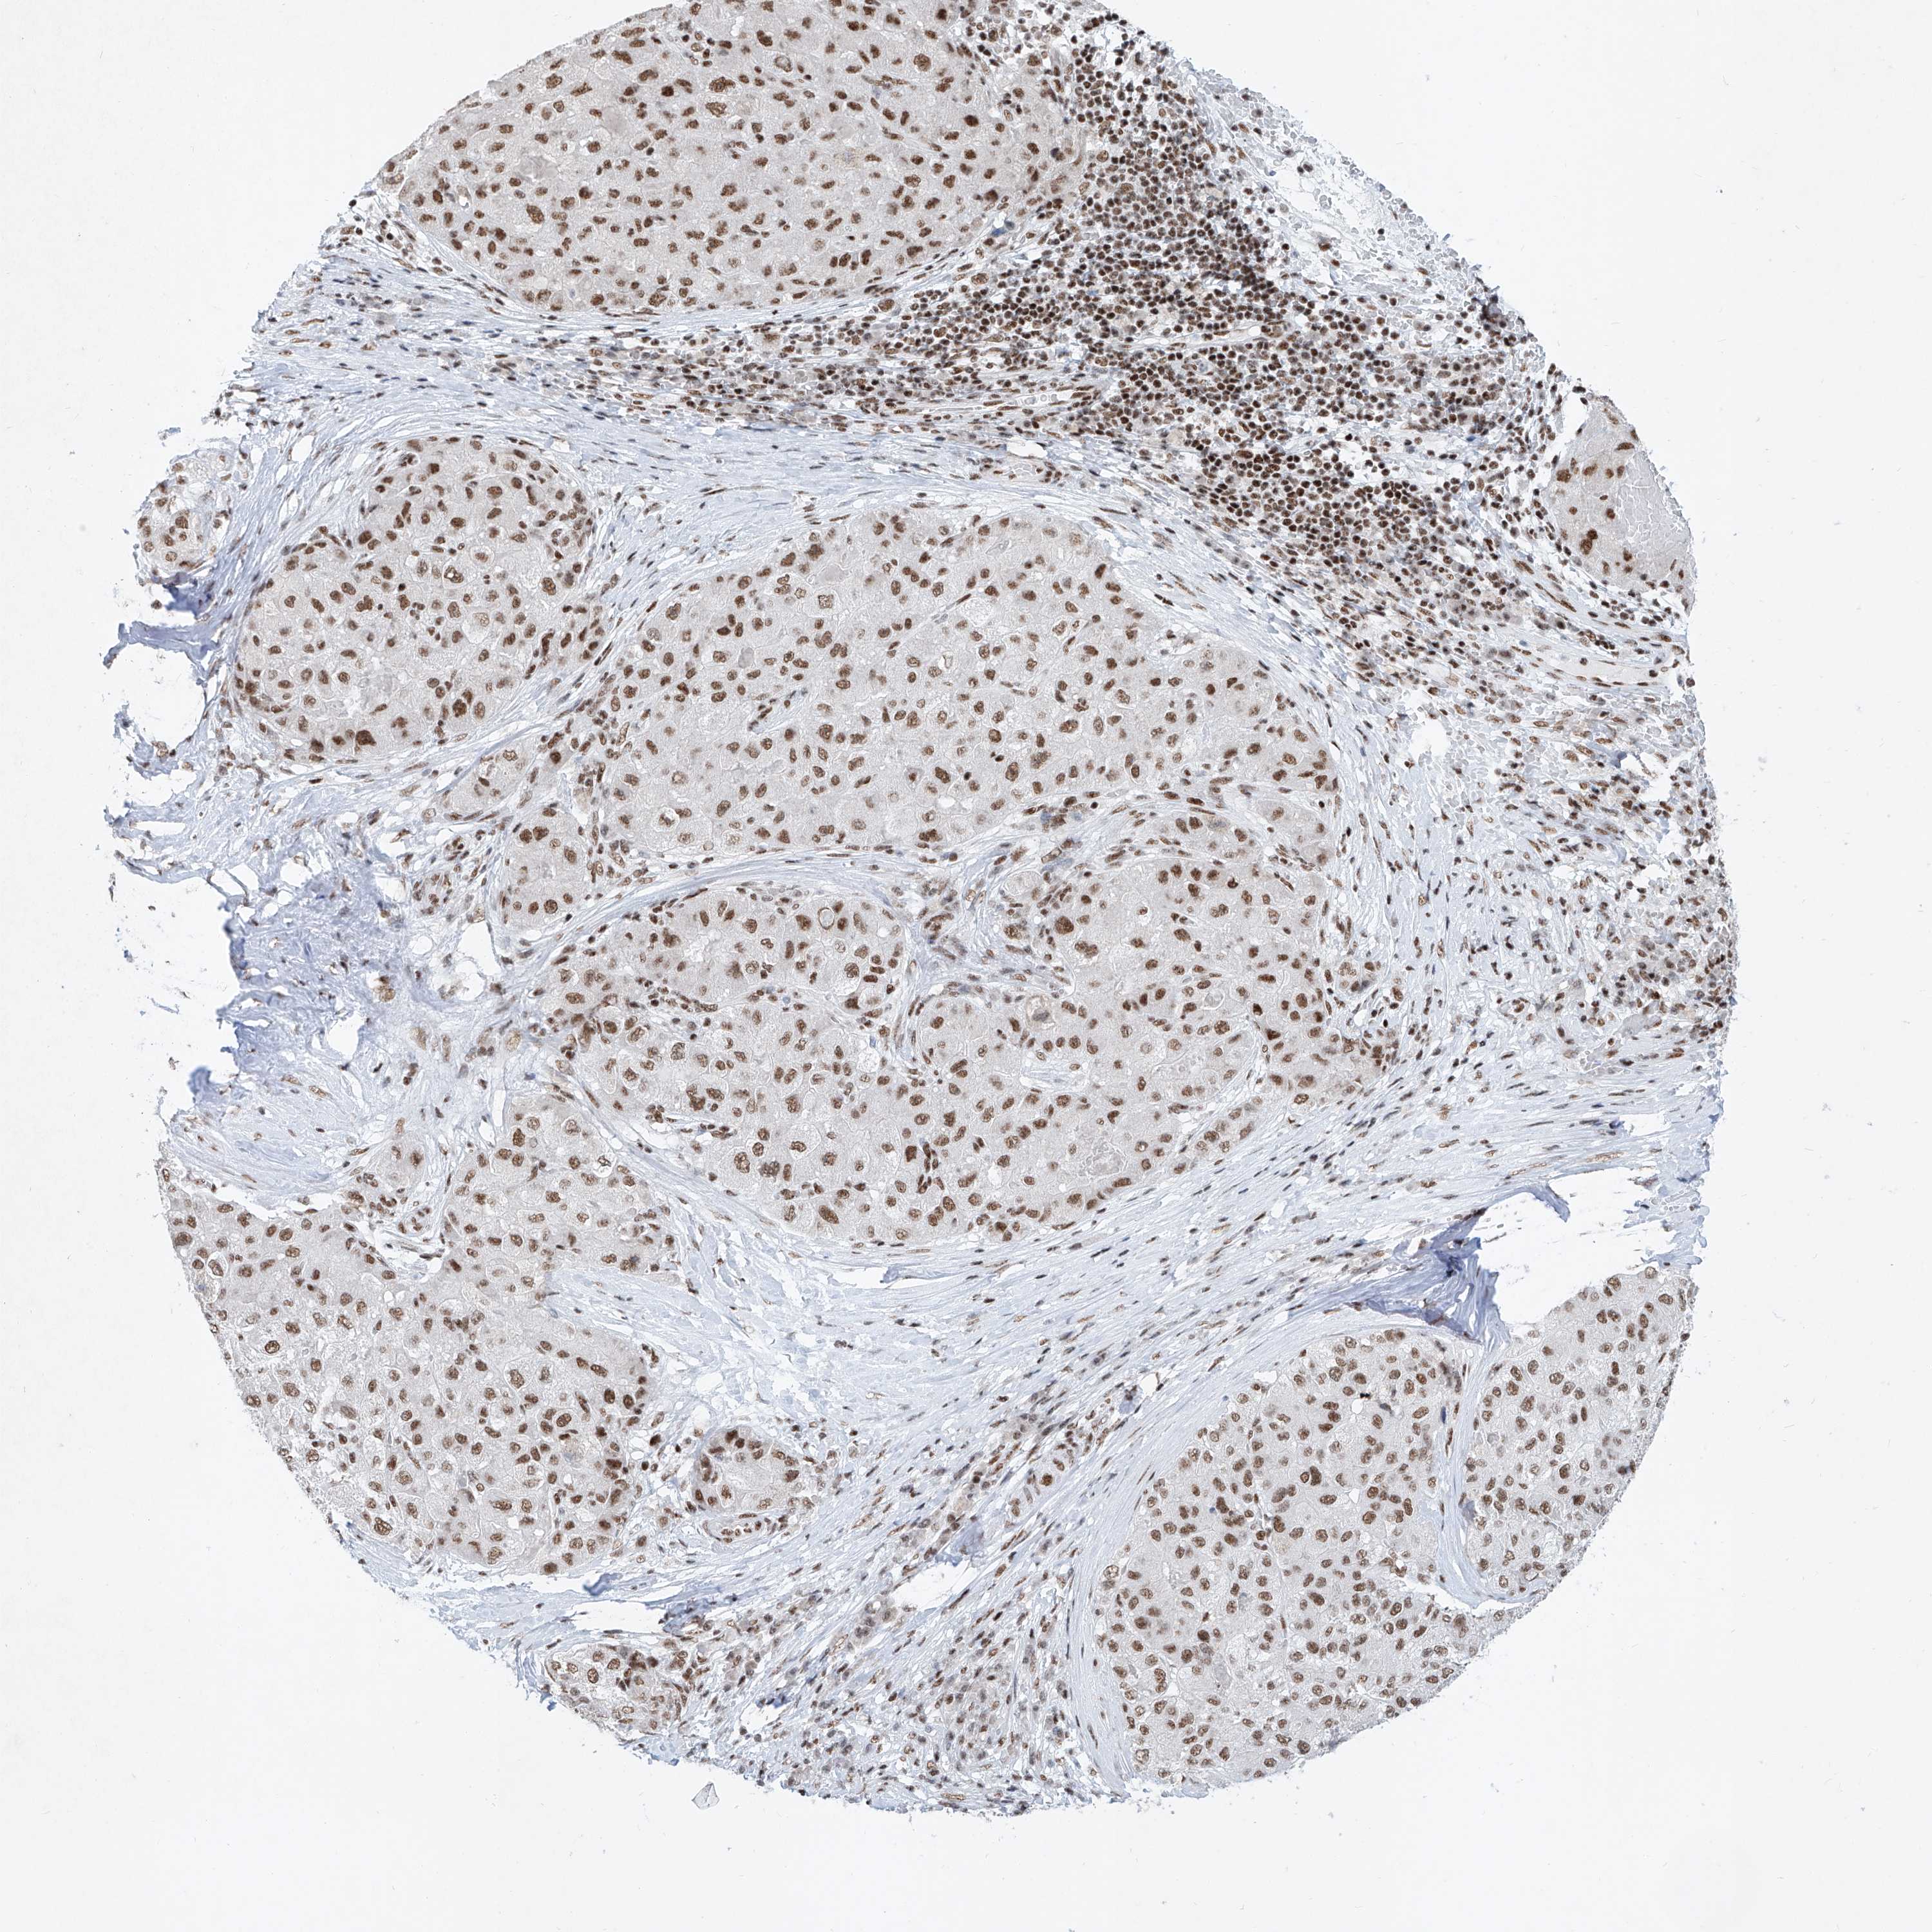

LIVER CANCER - Protein expressioni

A mouse-over function shows sample information and annotation data. Click on an image to view it in a full screen mode. Samples can be filtered based on level of antibody staining by selecting one or several of the following categories: high, medium, low and not detected. The assay and annotation is described here.

Note that samples used for immunohistochemistry by the Human Protein Atlas do not correspond to samples in the TCGA dataset.

Antibody stainingi

Antibody staining in the annotated cell types in the current human tissue is reported as not detected, low, medium, or high, based on conventional immunohistochemistry profiling in selected tissues. This score is based on the combination of the staining intensity and fraction of stained cells.

Each image is clickable and will lead to virtual microscopy that enables deeper exploration of all samples and also displays staining intensity scores, fraction scores and subcellular localization as well as patient and tissue information for each sample.

Antibody HPA008599

Antibody CAB031484

Staining

High

Medium

Low

Not detected

Intensity

Strong

Moderate

Weak

Negative

Quantity

>75%

75%-25%

<25%

None

Location

Nuclear

Cytoplasmic/membranous

Cytoplasmic/membranous,nuclear

Cholangiocarcinoma

Carcinoma, Hepatocellular, NOS